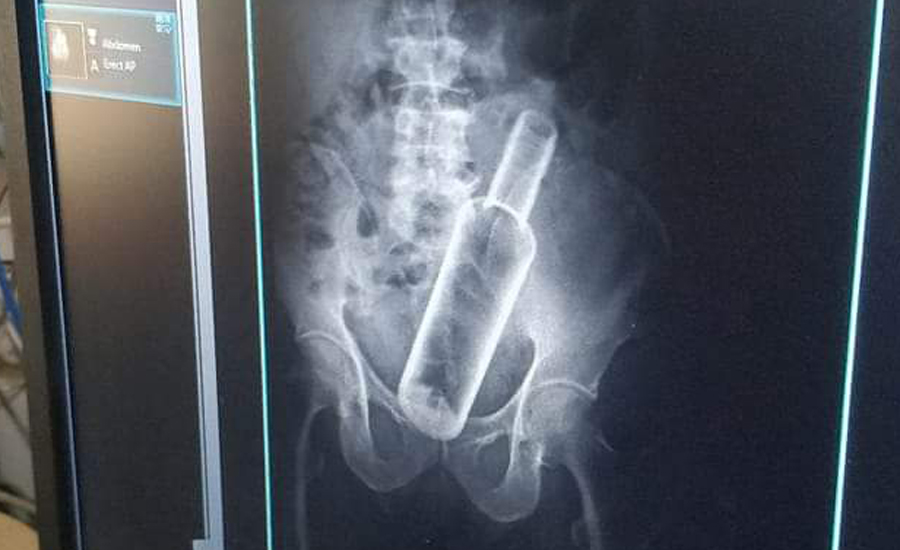

धनगढी । सेती प्रादेशिक अस्पतालमा उपचार गर्न गएका एक वृद्धको पेटमा बोतल भेटिएको छ । धनगढीको फूलबारी बस्ने ६१ वर्षीय जमनसिंह रोक्कामगरको एक्सरे गर्दा पेटमा रक्सीको बोतल देखिएको अस्पतालले जनाएको छ । प्रादेशिक अस्पतालका सूचना अधिकारी मेखराज उपाध्यक्षले दिएको जानकारी अनुसार बिहीबार पेट दुखेपछि अस्पताल आएका रोकामगरको एक्सरे गर्ने क्रममा बोतल देखिएको हो ।

उनकाअनुसार केहि दिनअघि मदिरा सेवन गर्ने क्रममा साथीले मलद्वारबाट बोतल पेटमा घुसाइदिएको बताएका छन् । उनको प्रादेशिक अस्पतालमा उपचार भइरहेको छ । यसअघि रौतहटका एक युवाको पेटमा पनि यस्तो बोटल भेटिएको थियो । चितवनको भरतपुरस्थित पुरानो मेडिकल कलेजका चिकित्सकले शल्यक्रिया गरी उनको पेटबाट बोतल निकालेका थिए ।